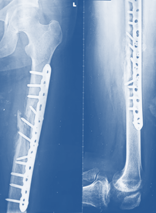

Thorough evaluation of patient was done and after 7 days of re-fracture, modified Ilizarov frame was mounted with plate in situ for treatment of the patient (Figure 4,5).

Figure 4 Post-operative x-ray after mount Ilizarov frame kept plate in situ.

After complete healing and consolidation of regenerated bone, substantiated by radiological evidence Ilizarov apparatus was dispelled 6 month later of installation without removal of plate (Figure 9). He was instructed to incur physiotherapy to recuperate range of motion (ROM) at the knee and hip joint.

Figure 9 Post-operative x-ray after removal of Ilizarov frame without removal of plate.

After 4 months of Ilizarov apparatus removal, there were no pin site wounds, ROM at knee was 0-1200 and normal hip motion. C- reactive protein (CRP) and erythrocyte sedimentation rate (ESR) were done 3 consecutive tests in a week of surgery, the values in normal range and did not increased, also intra-operative bacteriological culture was done to see deep seated infection. There was no evidence of infection. Finally plate was removed. In radiograph there was 150 angulation and 1cm shortening of left lower limb. After 6 months radiograph 130 angulation. One (1) year and four (4) months radiograph after plate removal, there was bone remodeling and 60 angulation with 1 cm shortening of left lower limb found (Figure 10,11).

Figure 10 X-ray after removal of plate and consolidation (1 year & 4 months later).